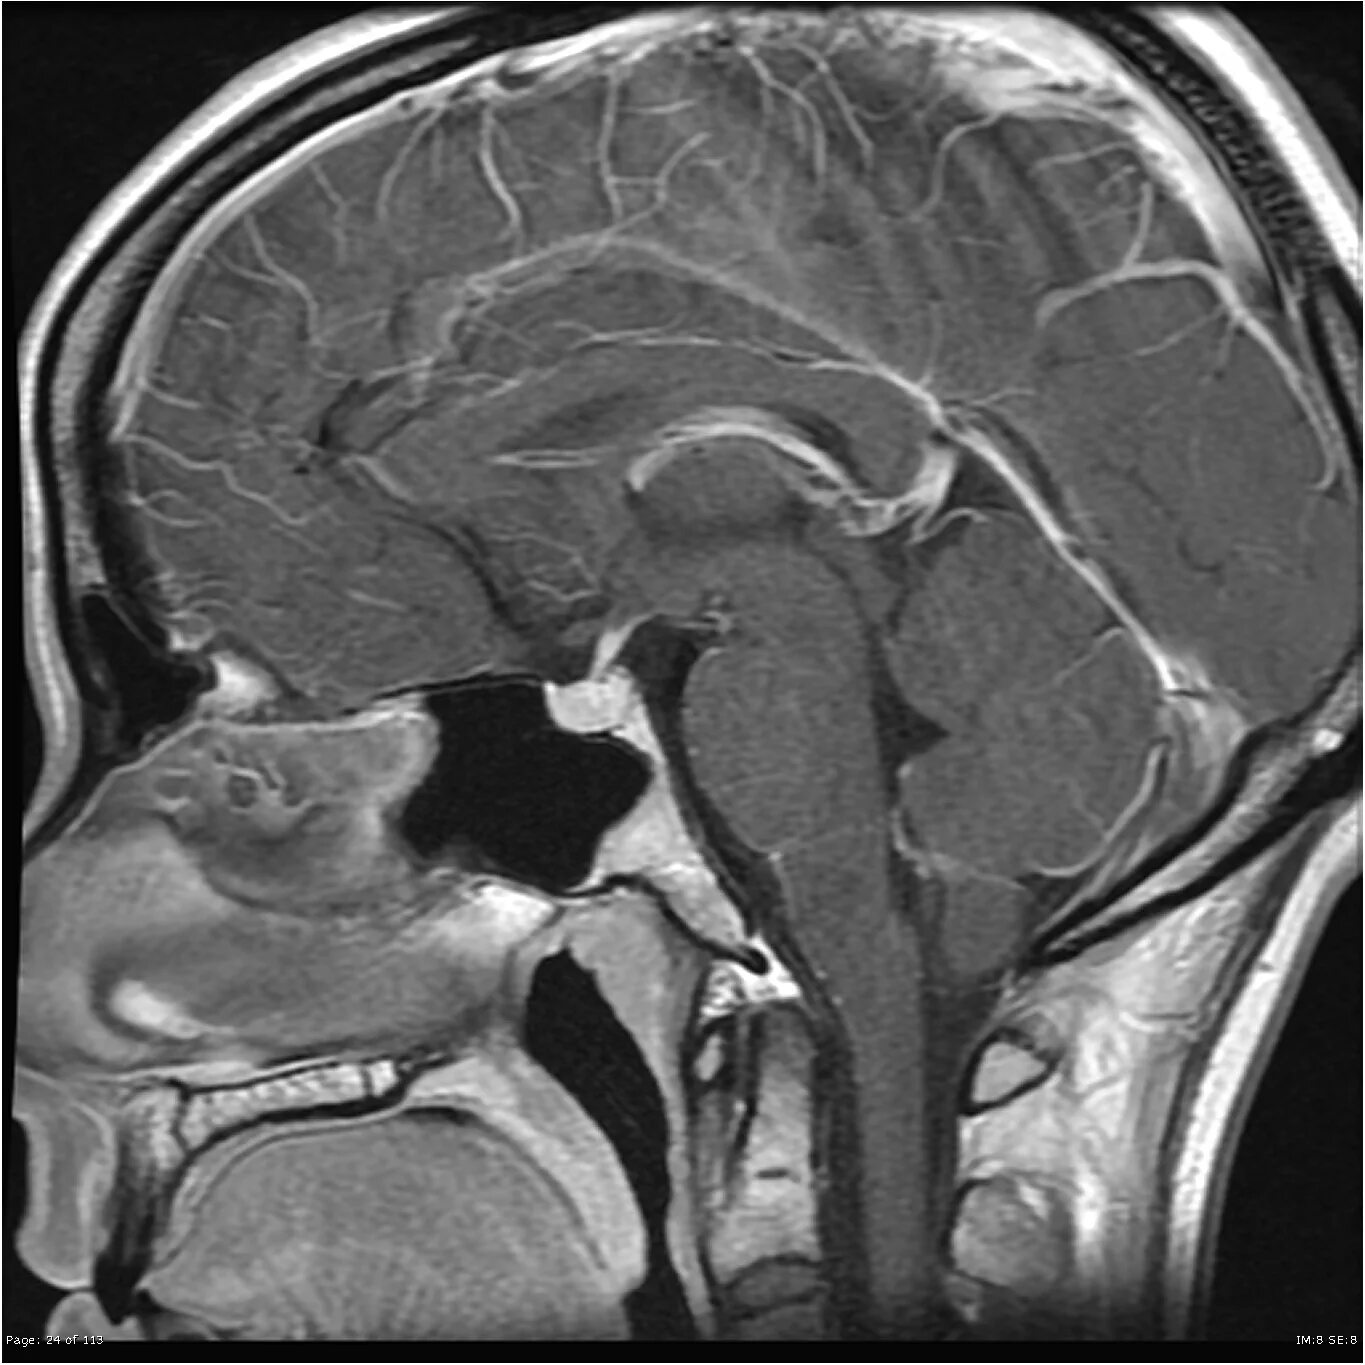

Опухоль гипофиза